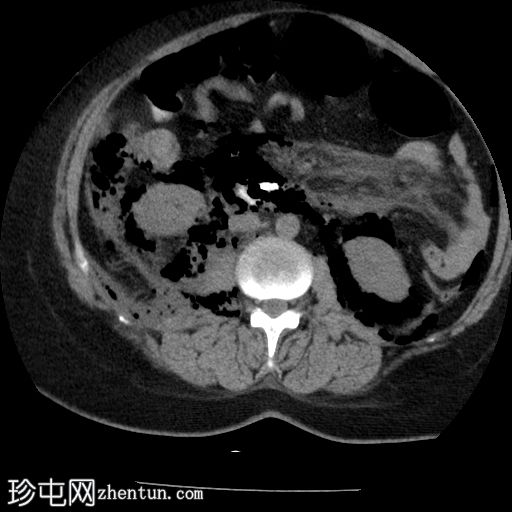

肺窗

4.jpg

轴位

口服增强

食管下三分之一处管壁均匀增厚,可见气泡(穿孔起始部位),纵隔及双侧胸膜腔内可见游离气体,提示食管穿孔。

十二指肠内可见造影剂早期渗漏至十二指肠旁间隙(第二个穿孔部位),同时主动脉旁、结肠旁、肾周及膈下区域可见游离气体,提示十二指肠穿孔。